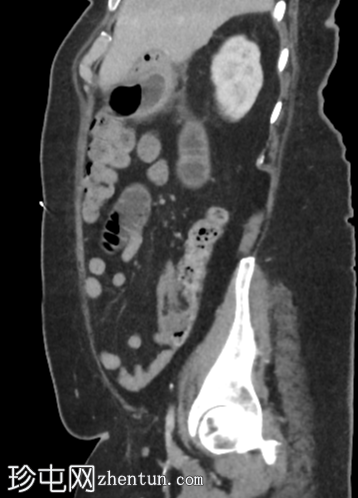

X线片

胃部因气体和液体而膨胀

小气囊突出于幽门外侧

圆形充满气体的脏器 - 因此不依赖胃部

小肠袢扩张